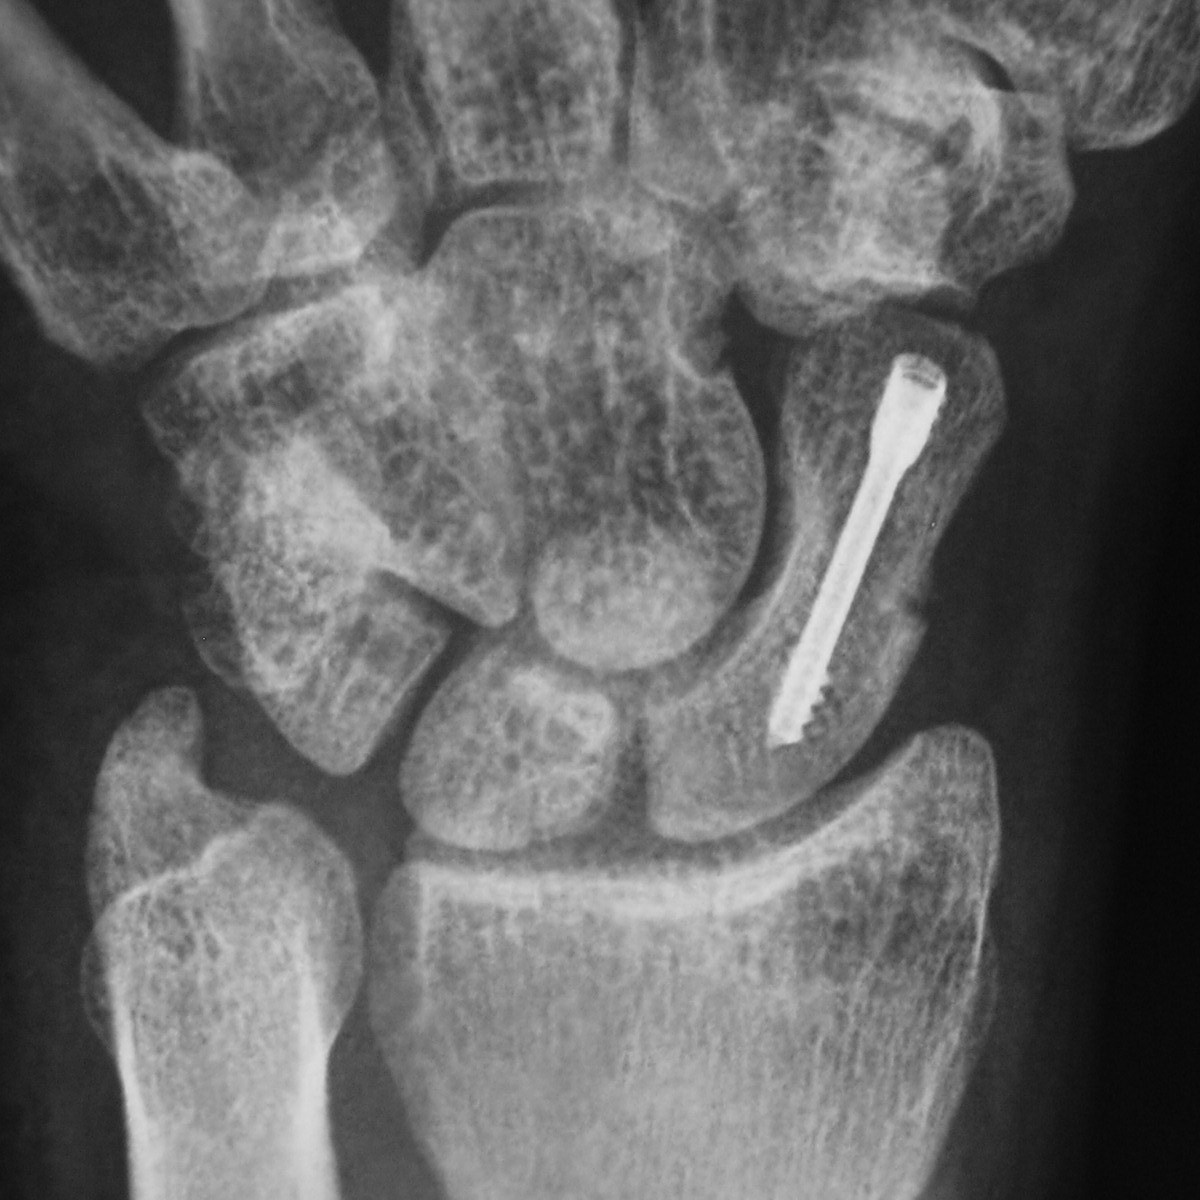

Scaphoideumfraktur

Symtom

Palpationsömhet i fossa Tabatiére, smärta vid axialt kompression av tummen samt vid dorsalextension respektive radialdeviation av handleden.

Drabbar ofta yngre individer i samband med sportutövning eller efter annat kraftigt dorsalextensionsvåld. Frakturen är ofta svår att identifiera på slätröntgen varför upprepade undersökningar och/eller CT/MR kan behövas.

Scaphoideum är dåligt vaskulariserad och ofta läker dessa frakturer (ffa proximala polfrakturer) långsamt; 3 månader i gips är normaltid! Gipsen skall immobilisera tumbas, handled och begränsa armens pro-supination. Utebliven läkning (pseudartros) är relativt vanligt och risken ökar om frakturen inte immobiliseras från skadetillfället.

Vid misstanke om scaphoideumfraktur (adekvat trauma, ömhet i fossa Tabatiére)

- Immobilisera i scaphoideumgips även om röntgen bedöms normal.

- Beställ då röntgenkontroll (utan gips) efter 10-14 dagar! Om röntgen är u a även efter 2 veckor, men status kvarstår: ordna snar MR- eller CT-undersökning!

Om skadan missas leder den mycket ofta till pseudartros och senare artros. En smärtsam pseudoartros kräver ofta att man tillför ben från crista illiaca vid operation och vid en handledsartros krävs någon typ av steloperation eller annat större ingrepp.

Det är tyvärr vanligt att frakturen missas då patienten kan uppleva symtomen som en distorsion, men det är också ganska vanligt att det missas av den undersökande doktorn. Detta sammantaget (s.k. 'patient's and doctors’ delay') innebär tyvärr att pseudoartrosoperationer är ganska vanliga.